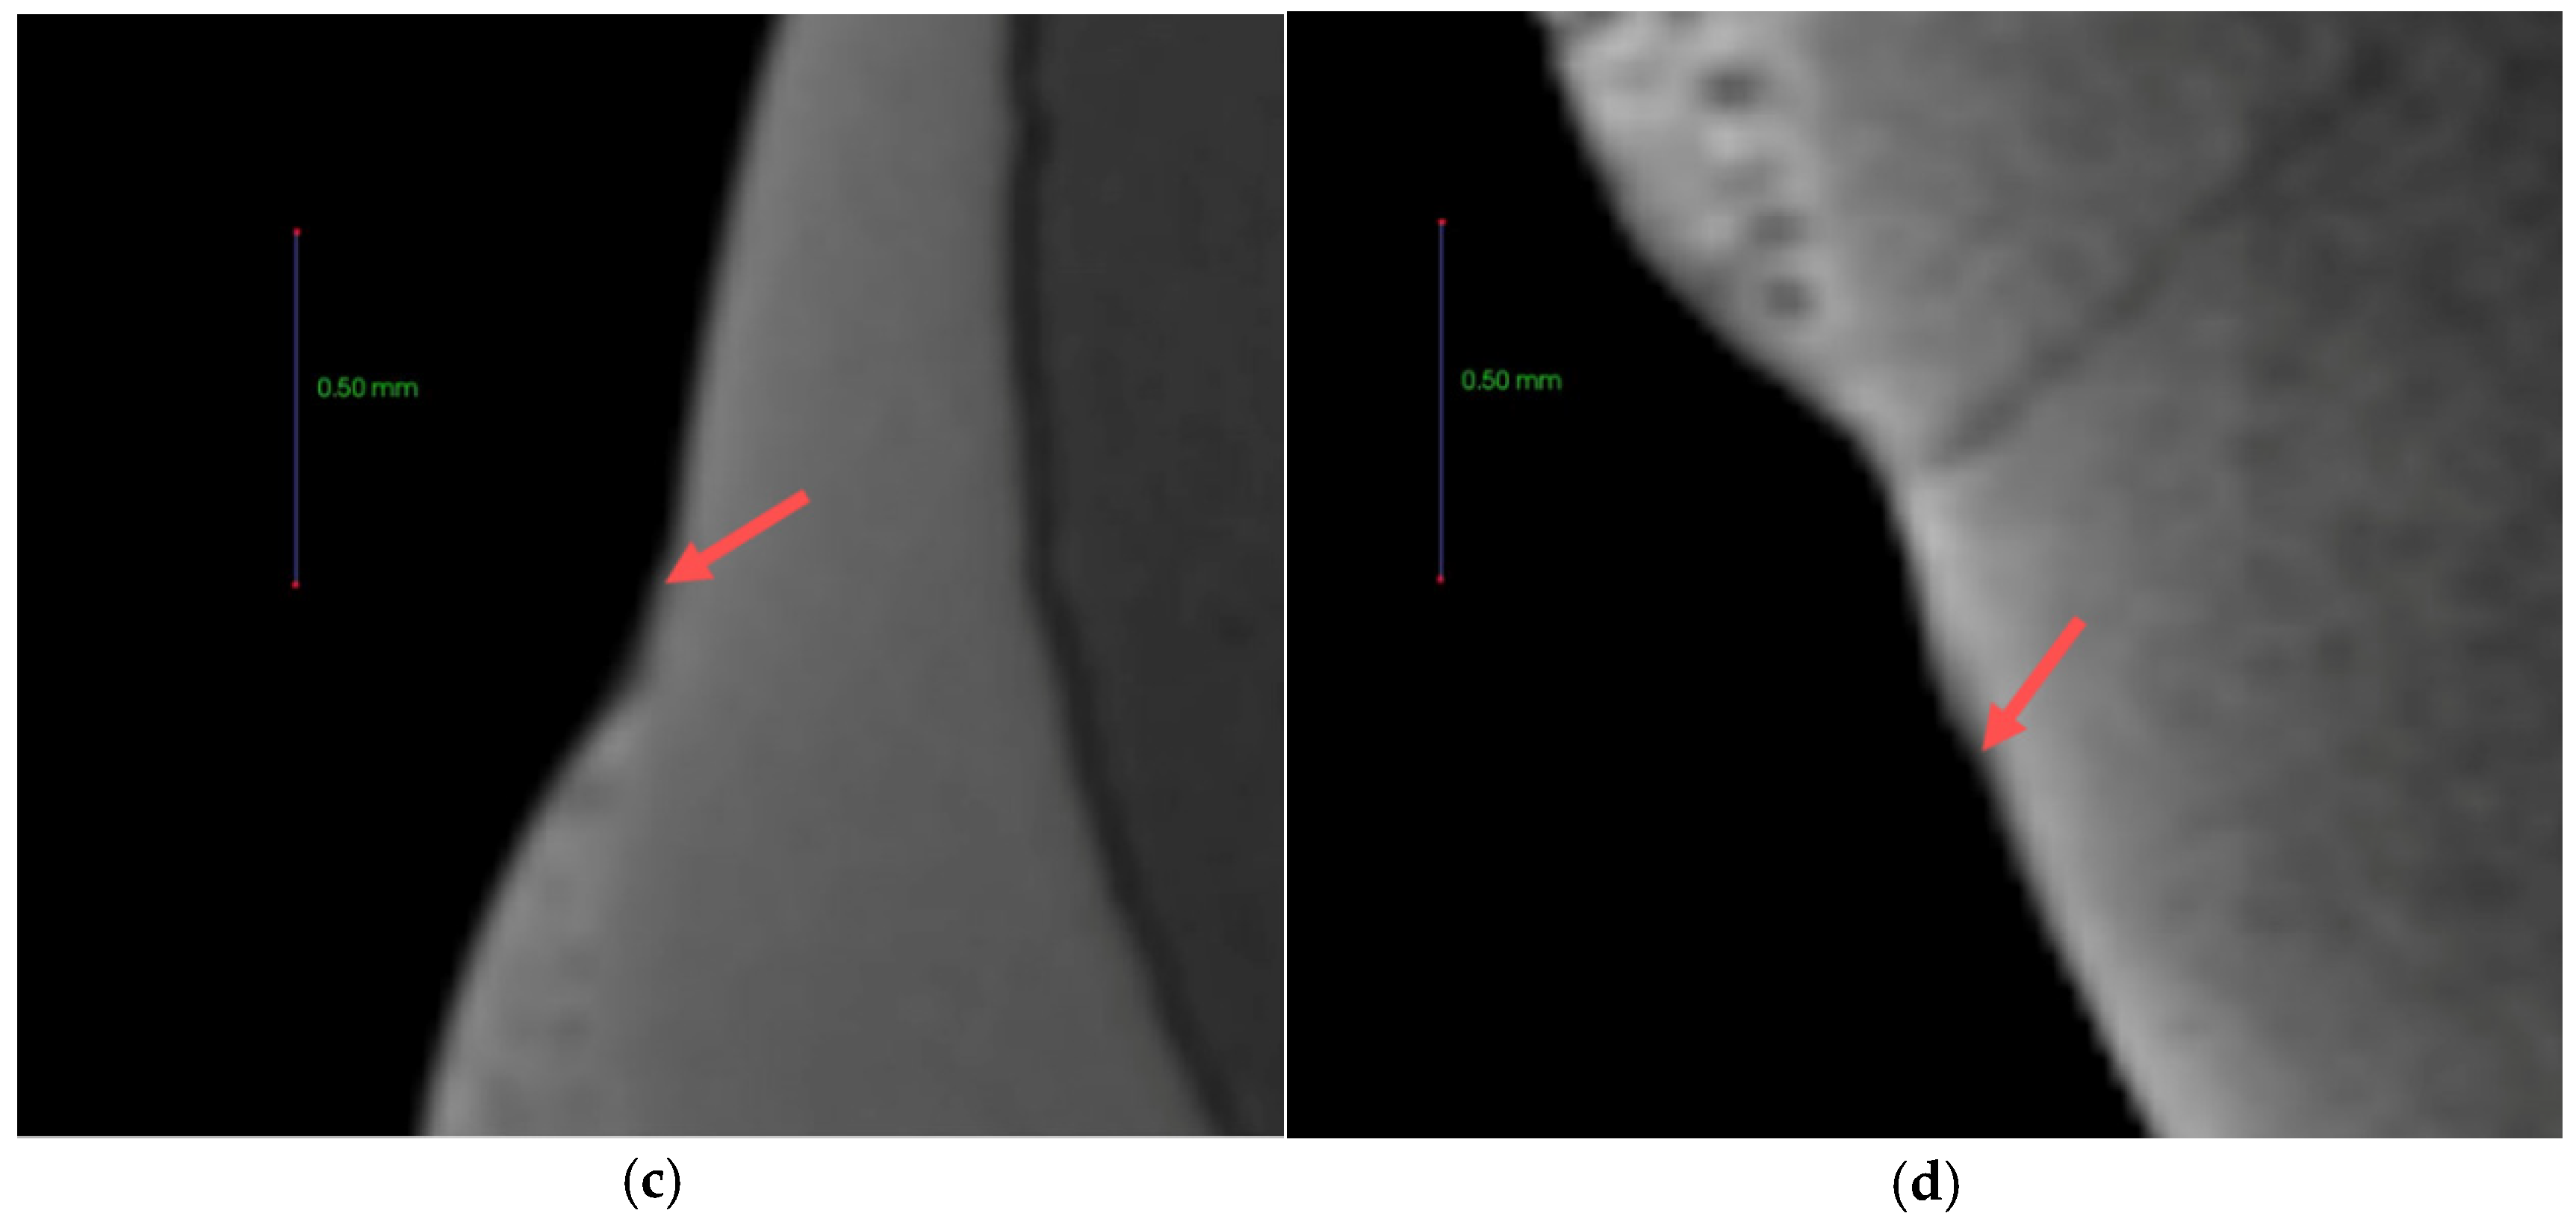

Each tooth was buried in acrylic resin (Caulk Orthodontic Resin, Dentsply Caulk, York, PA, USA) using a mold. The surface of the buried tooth sample to be bonded was rinsed with fluoride-free pumice and a prophylaxis cup, flushed for 10 s, and dried. To prevent etching except within the target 5 mm × 5 mm tooth surface, the vertices of the 5 mm × 5 mm square surface were clearly marked with nail varnish. The 5 mm × 5 mm tooth surface was etched for 30 s with 35% phosphoric acid gel (Ultra-etch, Ultradent, South Jordan, UT, USA), flushed for 10 s, and dried. The orthodontic bonding adhesive sample, which was manufactured using the same procedure as used for the disks, was applied to the surface and was light-cured for 5 s. The teeth were then immersed in distilled water for 24 h. The remineralization solution and demineralization solution were ordered to solution company by customized as Table 2. The samples were immersed in 500 mL of demineralizing solution (Biosesang, Seongnam-si, Korea) for 6 h, then washed distilled water 1 min, and finally immersed in 500 mL of the remineralizing solution (Biosesang, Seongnam-si, Korea) for 18 h. This immersion cycle was repeated for a period of 14 days. The solutions were replaced afresh once a week. The samples were washed with distilled water for 1 min and dried with gently-moving air before replacing the demineralizing and remineralizing solutions. The samples were measured using a micro-CT (InspeXio SMX-90CT Plus Benchtop Micro Focus X-ray, Shimadzu, Japan) at 90 kV and 109 μA. The measured micro-CT data were analysed using the ImageJ software program (National Institutes of Health, Bethesda, MD, USA) [20] (Figure 2). The scale was calibrated by the original micro-CT scale bar. The starting point was the end point of the sample orthodontic bonding resin. Using ImageJ, the length was adjusted in accordance with the scale bar on the micro-CT. Sound enamel was defined as comprising 87% gray value using a histogram, and the remineralization length was determined by measuring the distance from the end point of the sample orthodontic bonding resin to a point beyond the 87% gray value.

Figure 2.

Remineralization length analysis method. (a) Microcomputer tomography CT slice of the region of interest (ROI) at the center of the lesion perpendicular to the enamel surface. The starting point was the end of the adhesive, the green line is the line separating the ROI from a reference point on the enamel surface. (b) Histogram from the ImageJ software program. The blue arrow indicates up to a level of 87% gray value from the reference point, the red arrow indicates the distance to the 87% gray value from the reference point.

The anti-demineralization results (Figure 10 and Figure 11) showed that the anti-demineralization distances of FBAG1 (37.9 ± 7.7 μm), FBAG3 (50.4 ± 25.3 μm), and FBAG5 (229.3 ± 70.2 μm) were significantly larger than those of LV (14.7 ± 3.4 μm). Compared with LV, the group containing FBAG showed a significant different.

Figure 11.

87% gray value point from the reference point of the LV and FBAG orthodontic bonding adhesive via micro-CT. (a) LV; (b) FBAG1; (c) FBAG3; (d) FBAG5.